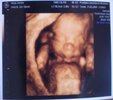

USG naszych Pociech

Tak się napatrzałam na te wasze piękne zdjęcia, że sama na pewno będę robić 4D, zdjęcia wszystkie robią wrażenie

Te zdjątka są boskie, już się nie mogę doczekać swojego USG 4d a to jeszcze tydzień. Ja też napewno pochwale się swoim skarbeńkiem

Oh, rozmarzyłam się patrząc na Wasze fotki z USG:tak::-). Ja w drugiej ciąży robiłam 3D i żałuję, że przy pierwszej na to nie wpadłam, miała by córa pamiątkę:rofl:. Cudne...

nasz dzidziuś:) USG z 13 tygodnia teraz już większy bo 16 tydzień :)))